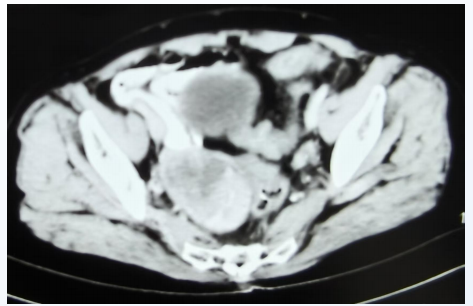

胸腹盆MRI(2021年8月24日)检查提示右侧附件区见密度减低影,大小约5.5*3.5cm,增强扫描实性部分明显强化,较前新发(图5)。

图5. 胸腹盆MRI检查(2021年8月24日)